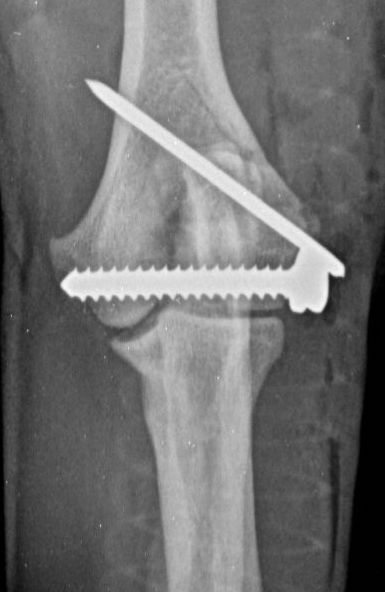

These concerns have led to recommendations being altered over the past decade or so, with veterinarians now using bone plates, instead of K-wires, as an adjunct to a transcondylar screw when managing humeral unicondylar fractures (Figure 2), even in puppies (Figure 3) (Clark, 2016; Kvale et al., 2022). However, the basis on which this conclusion for puppies was reached appears to have been flawed because it assumed that what had been shown to be the case for adults would also apply to immature patients. As the conclusion was felt to conflict with the author’s experience of treating such patients, a retrospective study was undertaken to evaluate complications and outcomes in immature dogs treated for humeral unicondylar fractures at one centre over a 10-year period (Butterworth, 2022). The findings of this study are summarised in this article.